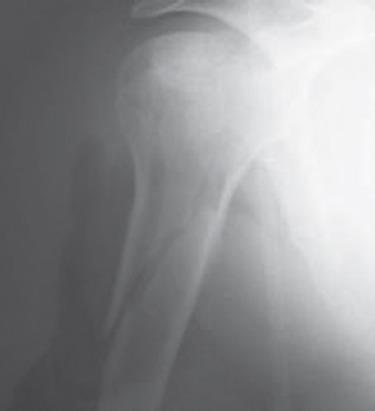

Ossifications after osteosynthesis of the proximal humerus are poorly described. We report a case of major and early ossifications after synthesis of a fracture dislocation of the shoulder.

A 57-year-old man, right-handed, bipolar schizophrenic, presented after a fall, a fracture of the head and metaphysis of the humerus from the anterior notch of posterior dislocation of the right humerus. An osteosynthesis was performed after reduction on the tenth posttraumatic day. The postoperative period was complicated because of early ossifications and painless stiffness of the shoulder.